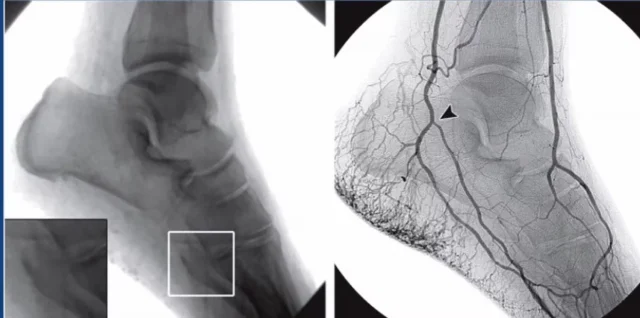

Bu hastalığın bir diğer ilginç yönü ise “bölgesel” ilerlemesidir. Yani bir damar boydan boya tamamen tıkanmak yerine, belirli kısımları hastalanırken aralarda sağlıklı kalmış damar bölümleri bulunur. Bu durum vücudun bir savunma mekanizmasını tetikler. Bedenimiz, tıkalı olan yolu aşmak için adeta yeni patikalar, yani yan damarlar (kollateraller) oluşturmaya çalışır. Bu yeni oluşan damarlar o kadar ince ve kıvrımlıdır ki anjiyografi dediğimiz damar filminde görüntülendiklerinde bir “tirbuşon”u andırırlar. Bu tirbuşon görüntüsü, Buerger Hastalığı için çok değerli bir tanısal ipucudur.

Bu adımlar arasında anjiyografi, tanıyı doğrulamada en değerli yöntemdir. Damarların içine özel bir boya maddesi verilerek çekilen bu filmlerde, Buerger Hastalığına özgü o “tirbuşon” benzeri ince yan damarlar, ana damarlardaki tıkanıklıklar ve hastalığın yayılımı net bir şekilde görülür. Tüm bu bulgular hastanın yaşı, sigara öyküsü ve şikayetleri ile birleştiğinde, tanı kesinleşmiş olur.